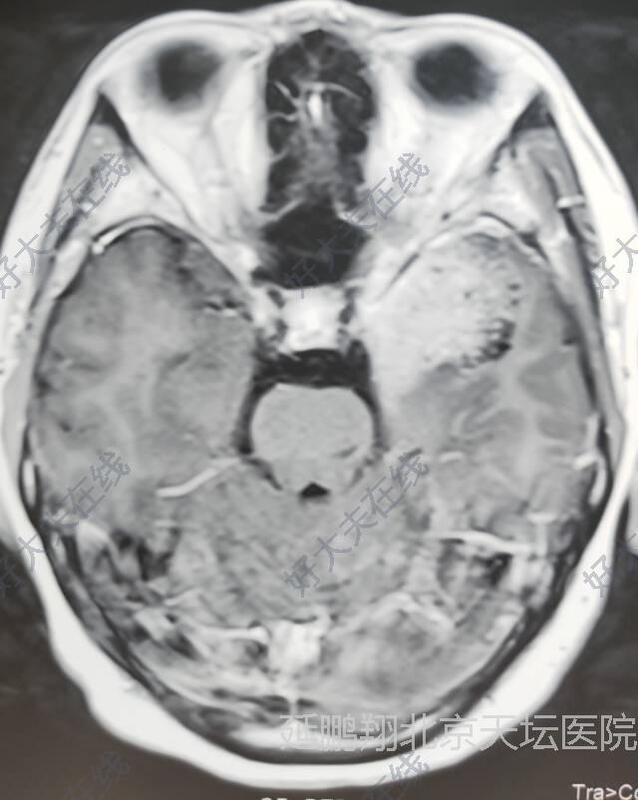

患者女性,38岁。间断性头痛3年左眼视力模糊1年。核磁显示左侧前床突脑膜瘤。

患者恢复顺利。复查核磁肿瘤消失。